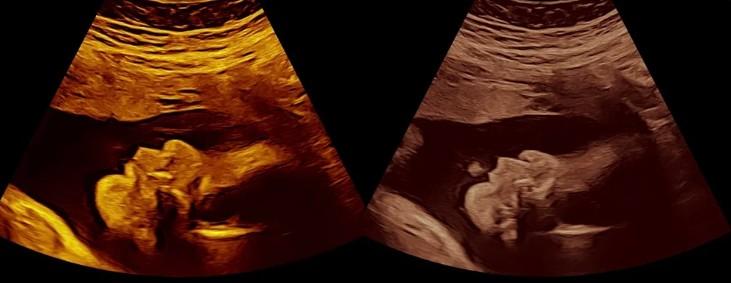

Pregnancy bonding ultrasound sessions offer families a beautiful opportunity to connect with their baby and create treasured memories before birth. Unlike medical scans, these non-diagnostic ultrasound sessions focus purely on enjoyment, celebration, and family connection. In Perth, a variety of specialised studios provide high-quality imaging in a calm, welcoming setting designed for parents-to-be.

The Technology Used for Bonding Ultrasounds

Modern imaging technology is used to create clear, engaging visuals for families to enjoy, without any diagnostic purpose.

• Real-time viewing of your baby’s movements

• Photo and video keepsakes without medical reporting